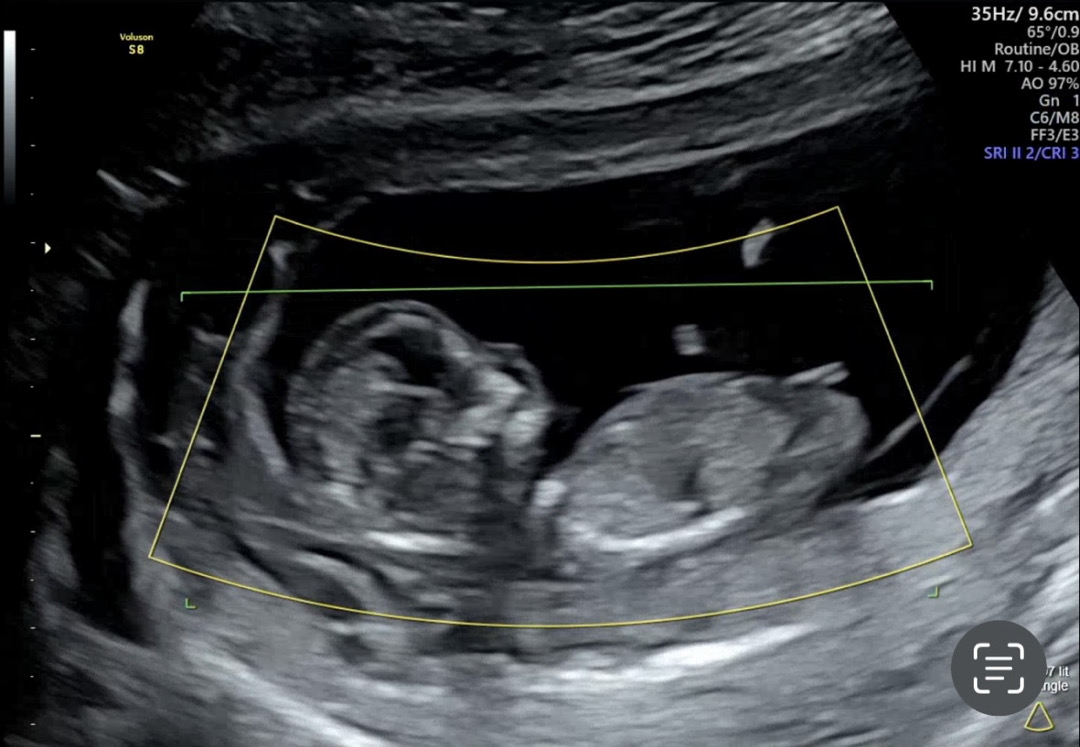

12주 성별 각도법봐주세요!

12주 기형아검사겸 입초랑 보고왓는데 입초에 아랫부분이 살짝 튀어나온거같아서 ㅋㅋㅋㅋㅋ 각도법으로 다시함번 부탁드려요!